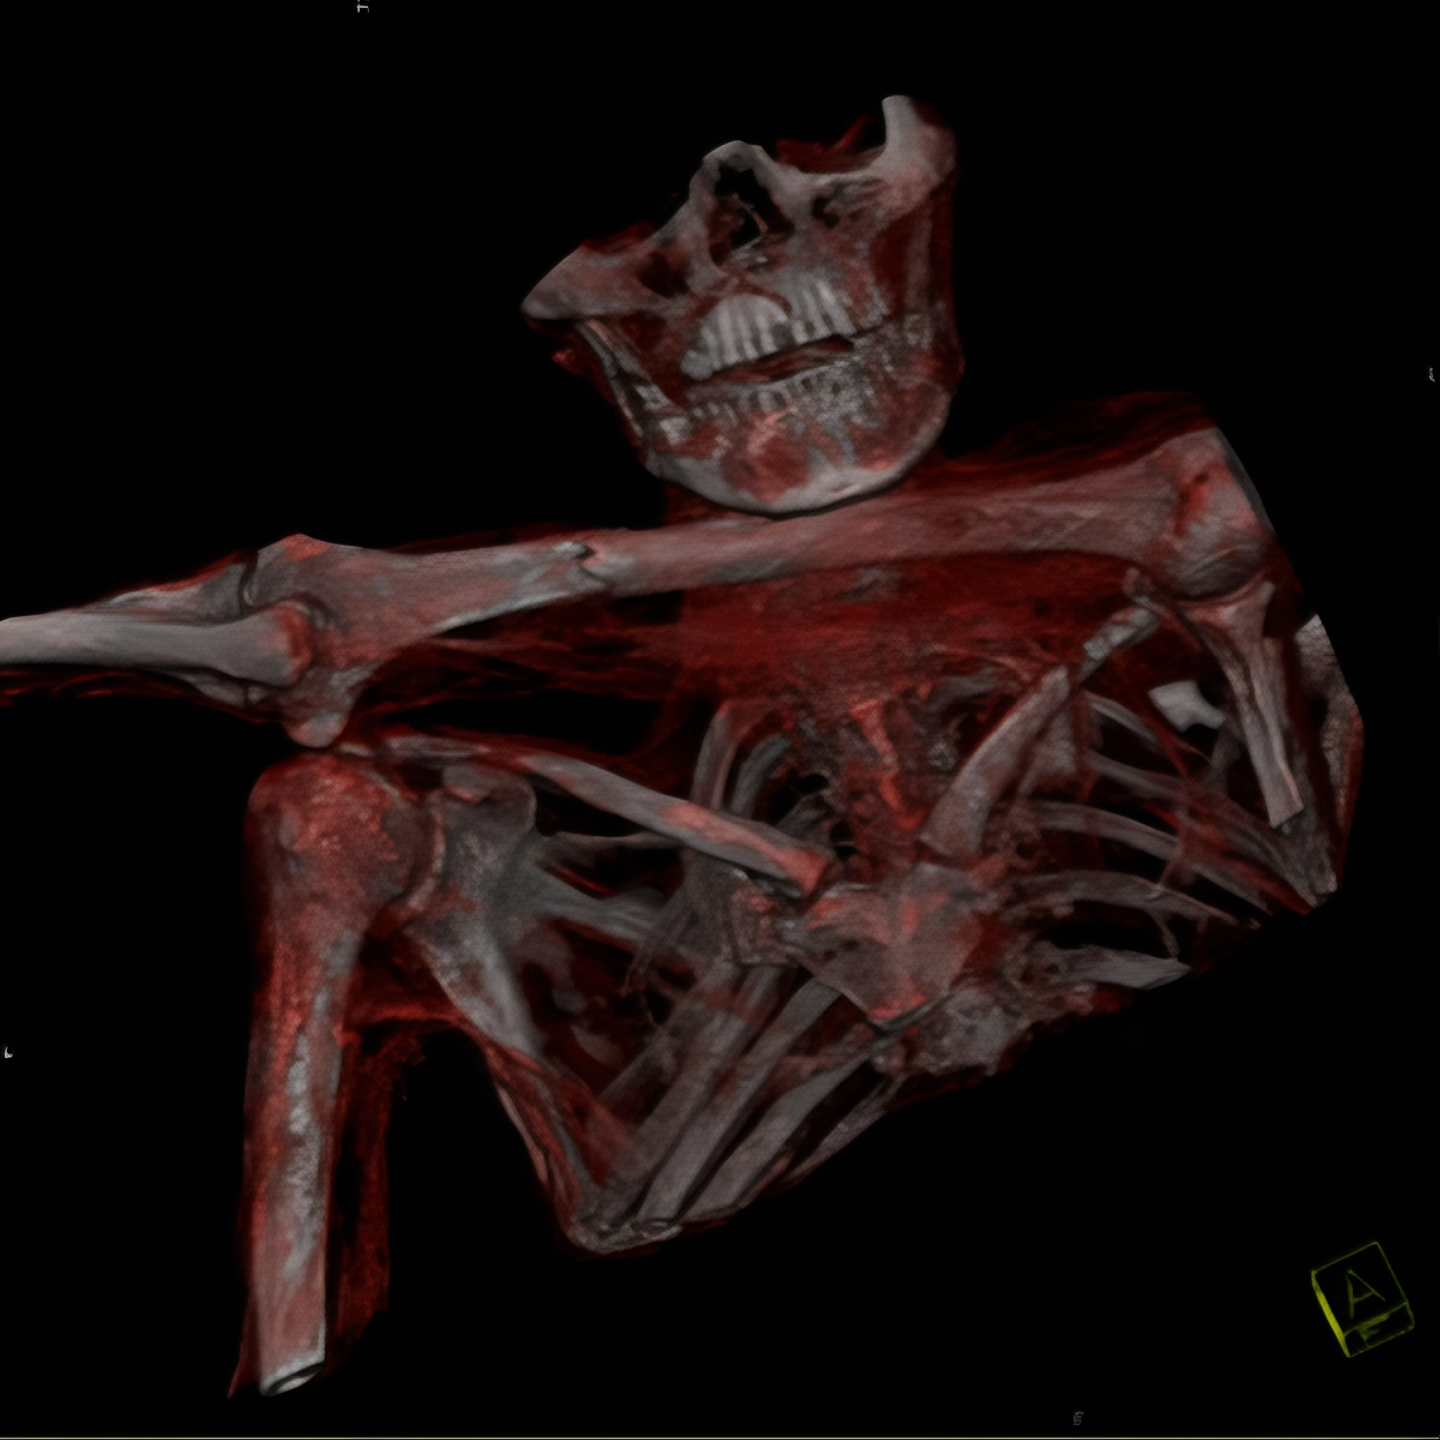

발견된 지 10년이 되던 2001년, 볼차노병원 방사선과 의사인 폴 고스트너 (Paul Gostner)는 외치에 대한 X선 검사를 시행하였는데 여기서 매우 수상한 소견을 발견한 것이다.

외치의 가슴 왼쪽 부분에서 정상적 소견이라고 볼 수 없는 음영을 찾았는데 그가 보기엔 아무리 봐도 인공물 같았다.

외치에 대한 CT 검사에서는 수상 한 부분이 더 두드러졌다.

그의 왼쪽 견갑골 부분에서 2 센티 정도 폭의 구멍이 발견된 것.

이 구멍은 그의 왼쪽 폐 언저리까지 뻗어 있었다.

이 조사에서 확인 된 것은, 외치의 몸안에 남아 있는 것은 돌로 만든 화살촉.

아마도 그는 죽기 전 누군가가 쏜 화살에 맞았을 터인데 그 뚫고 들어간 양상을 보면 왼쪽어깨 빗장밑동맥 (subclavian artery)을 건드렸을 것이다.